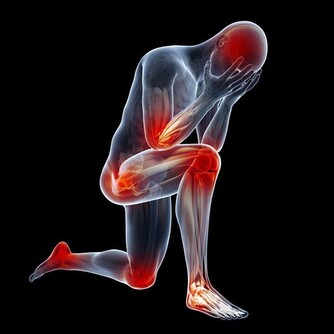

*****1.頭暈頭疼*****

早期的動脈硬化會出現頭暈頭疼的症狀,而且很多患者還會在額頭以及後腦勺的部位出現鈍疼,如果身體稍微活動還會出現頭暈的症狀,即便是再正常不過的走路也會走不穩定,經常會表現出眩暈以及眼球震顫的現象,還會出現不同程度噁心,即便是吞嚥也會受到影響。